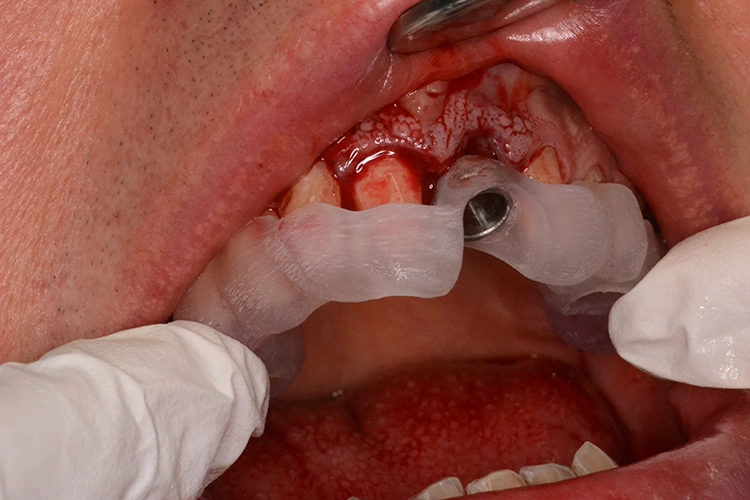

4. Sofortimplantation im Molarengebiet

Dr. Opitz

Aufgrund der Augmentation erfolgte die Freilegung 5 Monate postoperativ. Nach Ausformung des Emergenzprofils (Abb. 4i) erfolgte die definitive prothetische Versorgung durch eine okklusal verschraubte Einzelkrone (Abb. 4j).